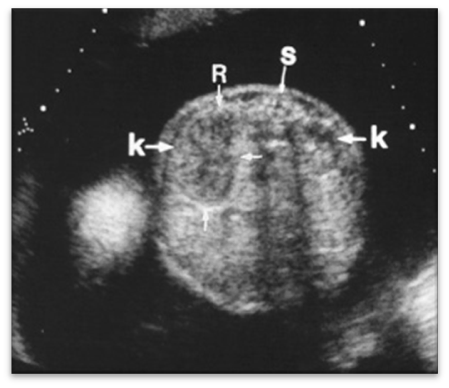

IPKD (ARPKD)